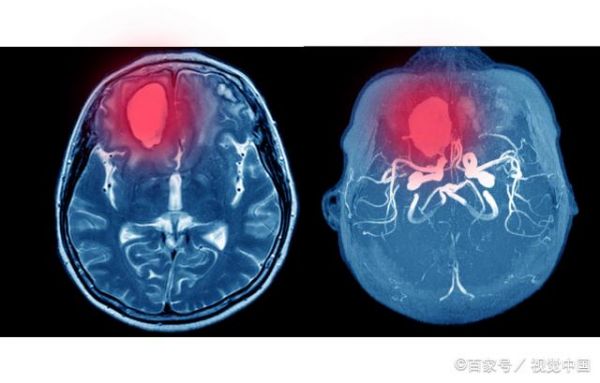

脑卒中是一种紧急情况,需要迅速而有效的医疗干预。当患者被送入急诊室时,急救医生会立即进行初步评估,包括检查症状、评估生命体征和进行神经检查。随后,医生通常会使用神经影像学技术,以确定脑卒中的类型和严重程度。这有助于医生确定是否为缺血性脑卒中(由血栓或栓子引起)或出血性脑卒中(由出血引起),因为治疗方法可能有所不同。

如果脑卒中是由血栓引起的,患者可能会接受溶栓治疗,这涉及到给予特定的药物以溶解血栓。在某些情况下,医生可能会考虑介入性手术,如血管内手术,以去除血栓或栓子。早期干预在急救和治疗阶段至关重要,因为它可以最大程度地减少脑损伤和提高康复的机会。